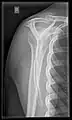

• Humerus - AP and Lateral